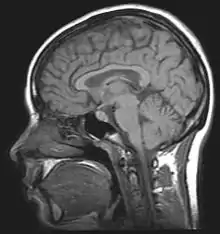

Neuroimaging is used to study the effect that alcohol has on the brain. The two main imaging methods are hemodynamic and electromagnetic. These techniques have allowed for the study of the functional, biochemical, and anatomical changes of the brain due to prolonged alcohol abuse.[2] Neuroimaging provides valuable information in determining the risk an individual has for developing alcohol dependence and the efficacy of potential treatment.[2][16]

Magnetic resonance imaging (MRI) and functional magnetic resonance imaging (fMRI) are other commonly used tenichiques. These methods are noninvasive, and have no radioactive risk involved. The fMRI method records the metabolic changes in a particular brain structure or region during a mental task. To detect damage to white matter, the standard MRI is not sufficient. An MRI derivative technique known as diffusion tensor imaging (DTI) is used to determine the orientation and integrity of specific nerve pathways, allowing the detection of damage.[2] When imaging those with alcoholism, the DTI results show that heavy drinking disrupts the microstructure of nerve fibers.[2] Another MRI derivative technique, magnetic resonance spectroscopy imaging (MRSI), can provide further information about the brain's neurochemistry and can detect the distribution of certain metabolites, neurotransmitters, and alcohol.